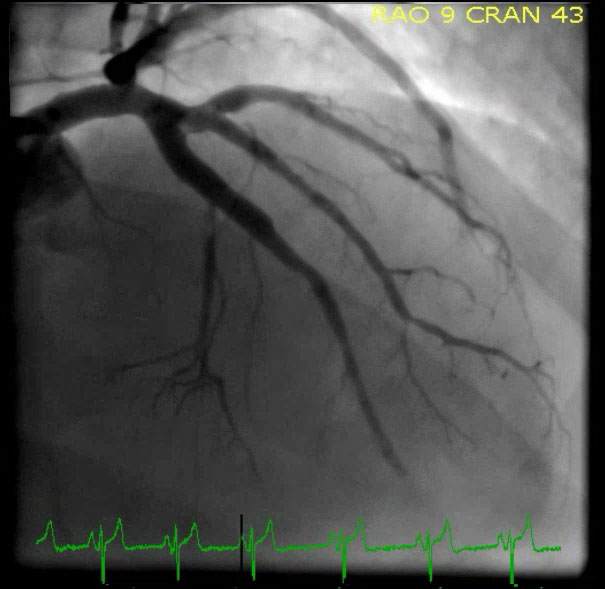

Пациент был взят на ангиографию.

Доктор Томпсон был прав, это был ИМО:

Была документирована 95% острая тромботическая окклюзия проксимального сегмента ПМЖВ с кровотоком TIMI-1.

Помните: Тромбы постоянно лизируются и вновь "прогрессируют", так что, если у вас нет ЭКГ с 12 отведениями, записанной в то же время, что и ангиограмма, нельзя точно сказать в каком состоянии находилась артерия во время регистрации ЭКГ. 95% окклюзия, в зависимости от состояния кровотока и множество других факторов (особенно наличие тромбоцитано-фибриновых сгустков ниже по течению, а также коллатерального кровотока) может проявляться разными морфологиями на ЭКГ. Независимо от того, полностью ли закрыта артерия или нет, ЭКГ (и боль) были динамическими, что доказывает наличие нестабильного тромба, который может распространиться и полностью закрыть сосуд в любой момент. Возможно, на момент регистрации ЭКГ была 100% окклюзия, но этого нельзя сказать наверняка. Все равно, хотя и имеется открытая артерия с сохраняющимся кровотоком, артерия подвержена риску полной окклюзии в любой момент.

Посмотрите, как ПМЖВ перегибается вокруг верхушки, объясняя, как ИМО может регистрироваться даже в нижних отведениях.

После вмешательства, кровоток TIMI 3.